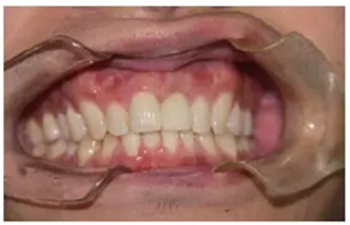

永久修復(fù)后3年進行回訪,種植體骨結(jié)合穩(wěn)定,美學(xué)效果良好。

圖14 永久修復(fù)3年后的回訪